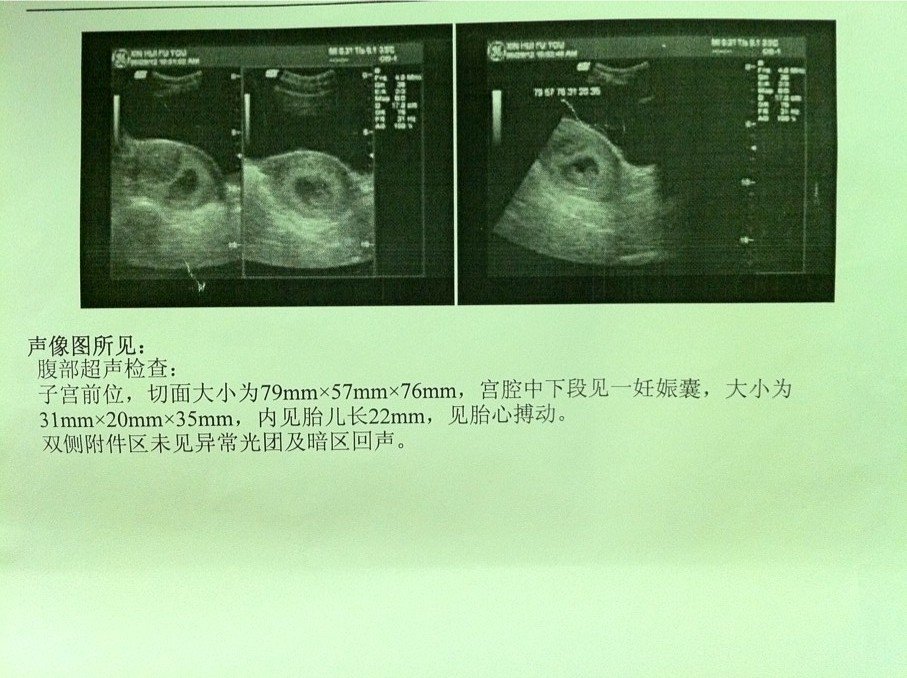

请问我的胎儿B超图正常吗?有医生又说胎盘位置低,不知道是不是有这情况呢?

正常的,这么小还不能说残迷胎盘的位置低不低,随着沙糕缘密乡怀孕月份加大,胎盘位置会上移的,不用担心。

真可爱,都可以看到小手小脚了乖乖 胎盘位置靠下月份大了容易早产,没有别的危险了,而且这风险也不高,月份大了就结实了而且会上移。 该怎么着就怎么着没事,等他长大前你注意少磕碰~~

B超单子上没写明胎盘位置.不过真低就很危险.详细咨询下医生吧.